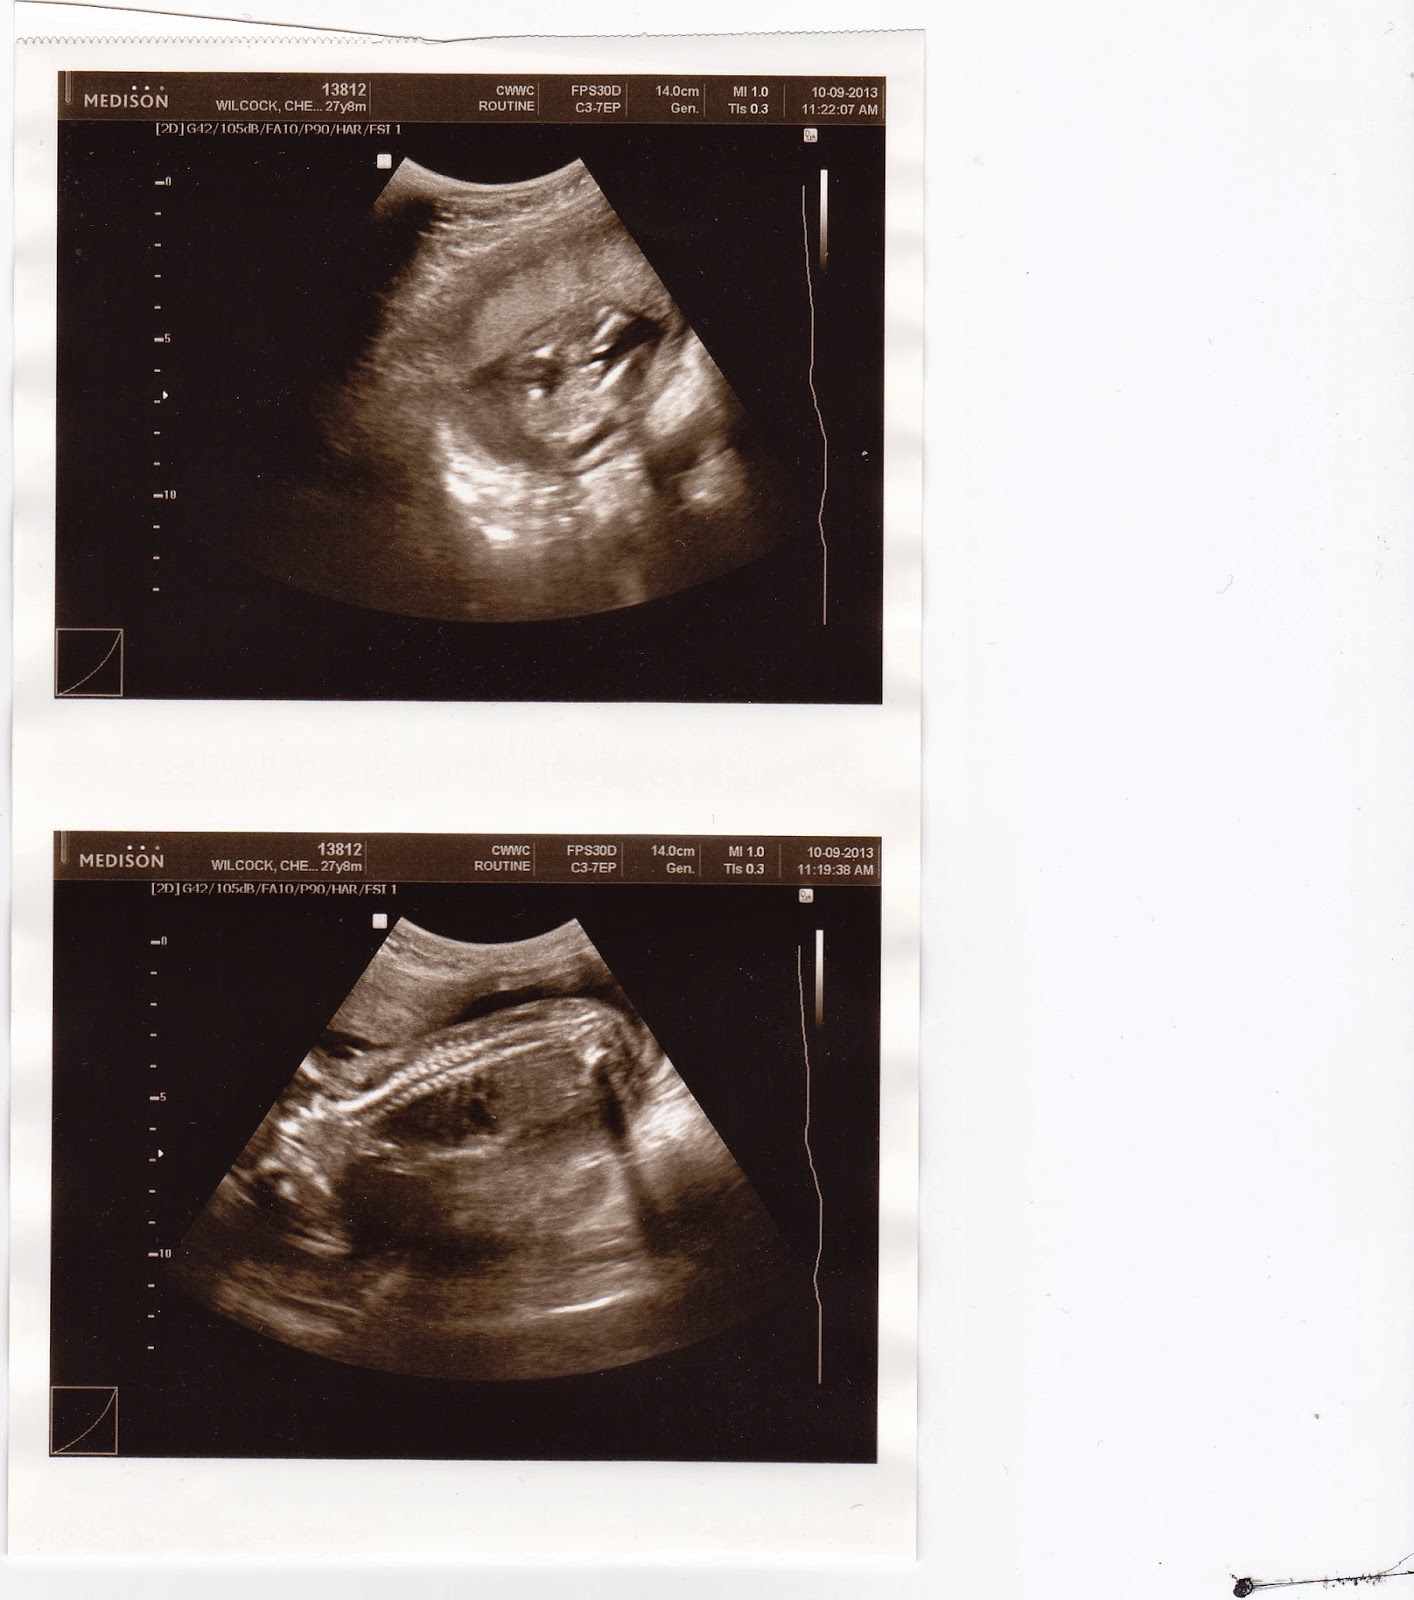

...BOY (first picture shows the "parts"). O, life. I hope mom is ready for this. At this point, mom is almost 23 weeks along and the pregnancy continues to go well.